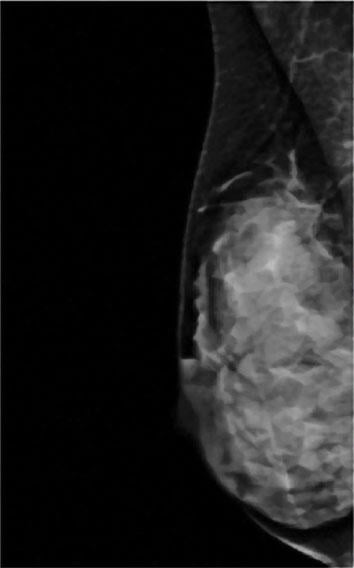

A comparision of a small breast cancer found in a patient without dense breast tissue (left), and a tumor found in a woman with dense fibroglandular tissue. For more information visit DenseBreast-info.org.

Roughly 40 percent of women of mammographic age (40 and older) fall into the last two categories, which are collectively considered dense. As density increases, it becomes more difficult to distinguish tumors and other masses from the surrounding tissue. Apart from this masking effect, dense breast tissue is itself a risk factor for developing breast cancer. Statistical evidence indicates that women with dense breasts are four to six times more likely to develop breast cancer than women with fatty tissue; they are also 17 times more likely to develop interval cancer (detected or presenting less than 12 months following a normal mammogram).